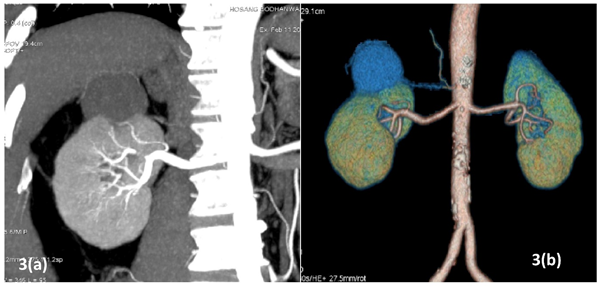

All patients underwent pre-operative contrast-enhanced computed tomography (CECT) of abdomen with renal angiography for tumour and vascular anatomy with 3D reconstruction (Figure 1). Routinely ipsilateral ureteric catheter was placed after anaesthesia. Surgical steps that were sequentially followed in all cases included ipsilateral colonic mobilization along with identification of ureter, gonadal vessels and psoas muscle; identification and mobilization of the renal artery and vein; mobilisation of the upper pole according to the need; demarcation of the tumour boundary with the help of intraoperative ultrasound; hilar clamping (renal artery and vein separately clamped); resection of the tumour; two layered renorrhaphy (Figure 2) with barbed suture with application of haemostatic agents (Gelatin granules with human thrombin and oxidised regenerated cellulose) and peri-renal drain placement. Zero-ischemia RPN were performed premeditatedly for cases with small (<4cm) cortical renal mass (predominantly exophytic) in favourable positions (lateral, lower and upper pole) and where single isolated feeder vessel was well identified (Figure 3). Ipsilateral ureteric catheter was removed routinely on 2nd post-operative day. We replaced the ureteric catheter with double-J stent where pelvicalyceal system were opened intraoperatively or tumour was larger one in vicinity to the pelvicalyceal system.

Figure 2 Renorrhaphy (barbed suture fixed with weck clips, oxidized regenerated cellulose mesh put at the raw site).